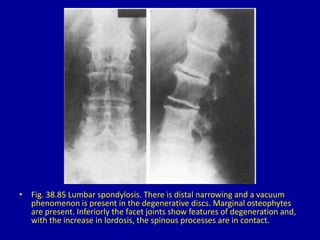

• Fig. 38.85 Lumbar spondylosis. There is distal narrowing and a vacuum

phenomenon is present in the degenerative discs. Marginal osteophytes

are present. Inferiorly the facet joints show features of degeneration and,

with the increase in lordosis, the spinous processes are in contact.

• Fig. 38.85Lumbar spondylosis. There is distal narrowing and a vacuum phenomenon is present in the degenerative discs. Marginal osteophytes are present. Inferiorly the facet joints show features of degeneration and, with the increase in lordosis, the spinous processes are in contact.